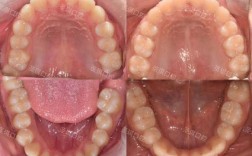

横腭杆的主体通常由直径0.9-1.2mm的不锈钢丝弯制而成,呈“U”形或弧形,两端通过焊接或直接插入预先粘固于上颌第一磨牙(有时包括第二磨牙)带环的舌侧管中,从而实现与两侧磨牙的刚性连接,其结构虽看似简单,但需根据患者的腭部形态、牙弓宽度及治疗目标进行个性化定制,以确保与口腔软组织贴合,避免压迫腭部黏膜,同时发挥有效的力学传导作用,以下是横腭杆主要结构组成的详细说明(见表1)。